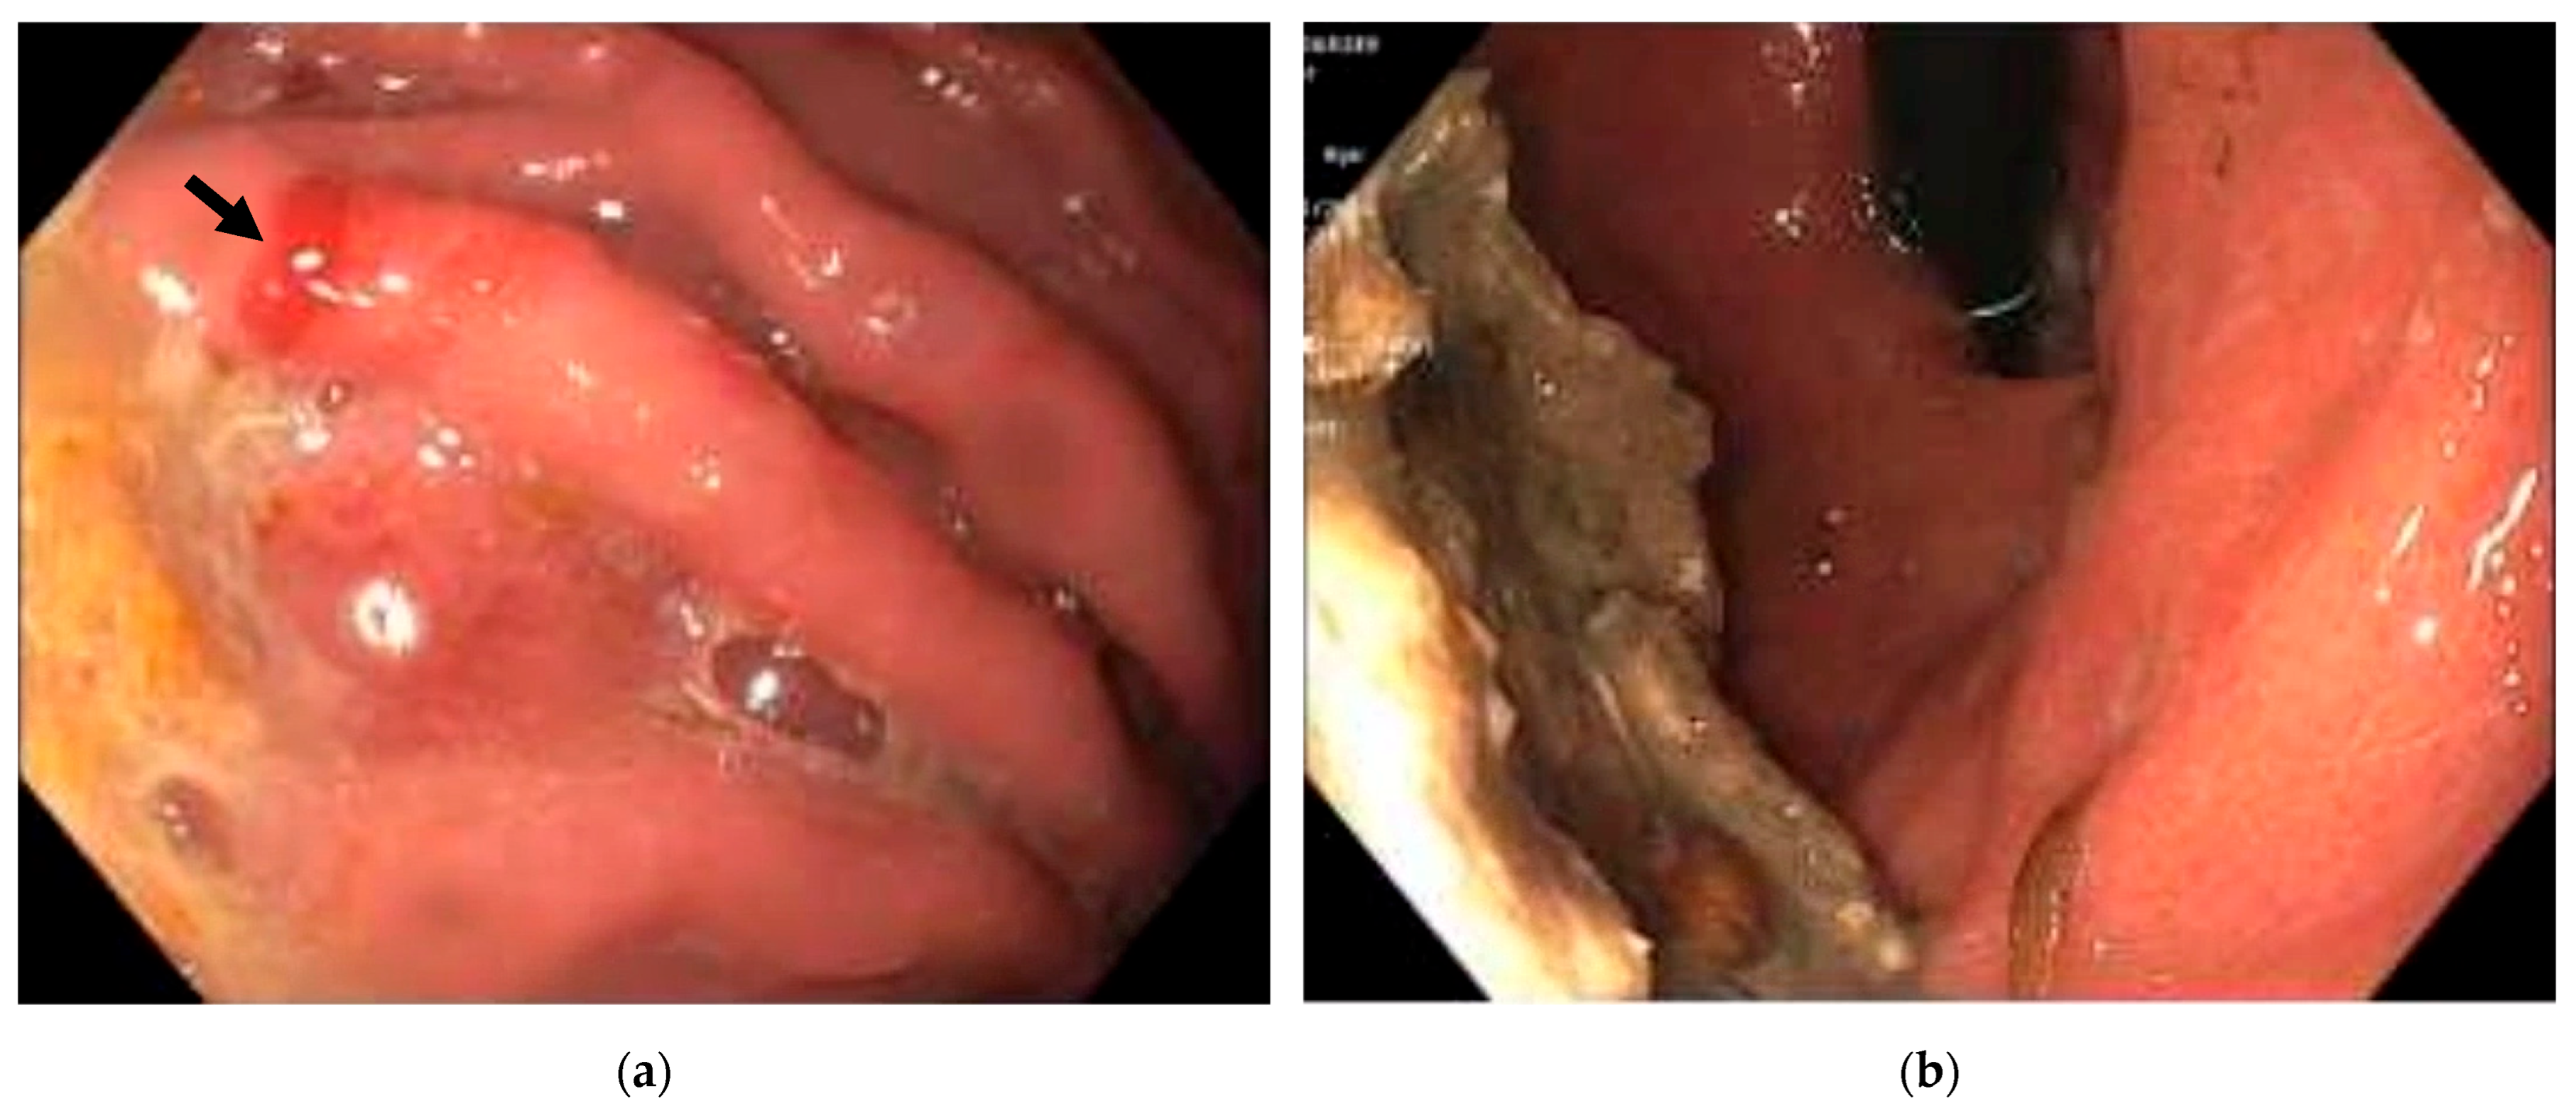

2. Case Presentation